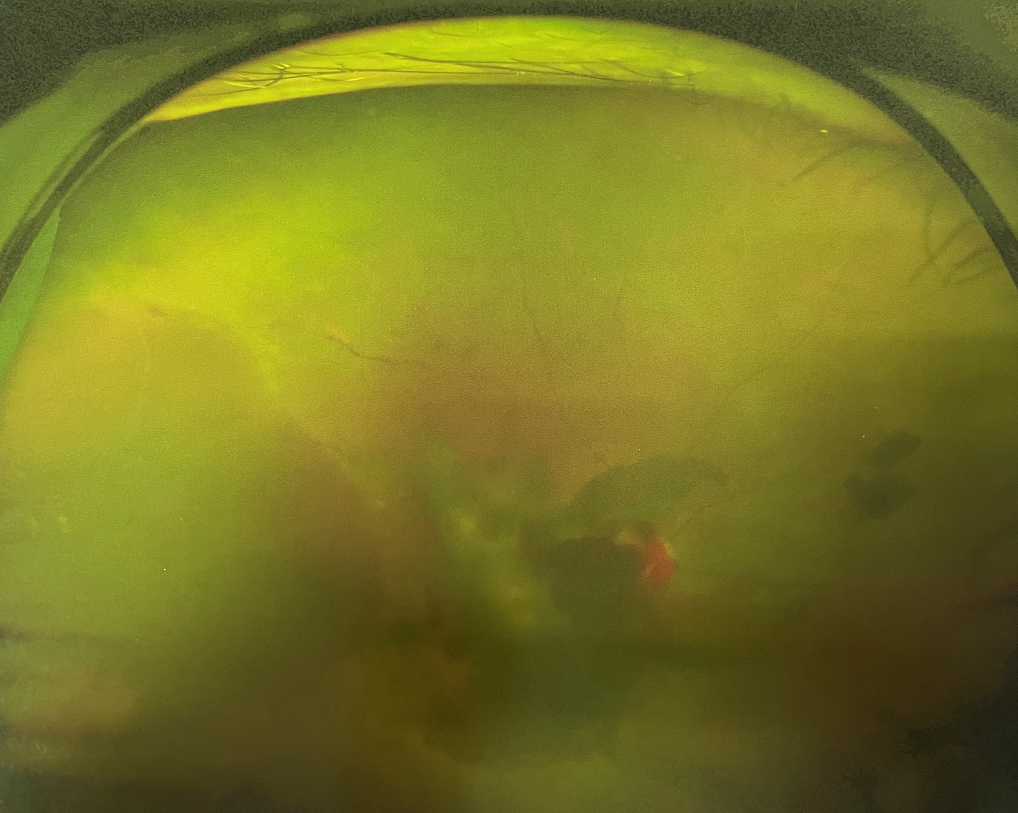

右眼術(shù)前

眼底病專(zhuān)科張小虎醫(yī)生檢查后,診斷王女士為“雙眼玻璃體積血、雙眼糖尿病視網(wǎng)膜病變V期”。(V期即5期,纖維增生期,出現(xiàn)纖維膜,可伴視網(wǎng)膜前出血或玻璃體出血。)

張小虎醫(yī)生為王女士進(jìn)行右眼玻璃體腔注藥術(shù),3天后進(jìn)行右眼23G玻璃體切割術(shù)后視力有所提升。

4個(gè)月后王女士來(lái)院取硅油,取油后視力恢復(fù)到0.6。“當(dāng)時(shí)來(lái)的時(shí)候真的只能看到模糊的影子,特別害怕覺(jué)得完了,想說(shuō)眼睛估計(jì)要瞎了,沒(méi)想到手術(shù)后視力竟然提升了,現(xiàn)在也看得比較清楚了。”王女士說(shuō)到。

張小虎醫(yī)生表示,糖網(wǎng)病進(jìn)展到嚴(yán)重增殖期帶來(lái)的視力損傷往往是極其嚴(yán)重的,目前王女士右眼從術(shù)前0.02恢復(fù)到術(shù)后0.6,已屬十分難得。